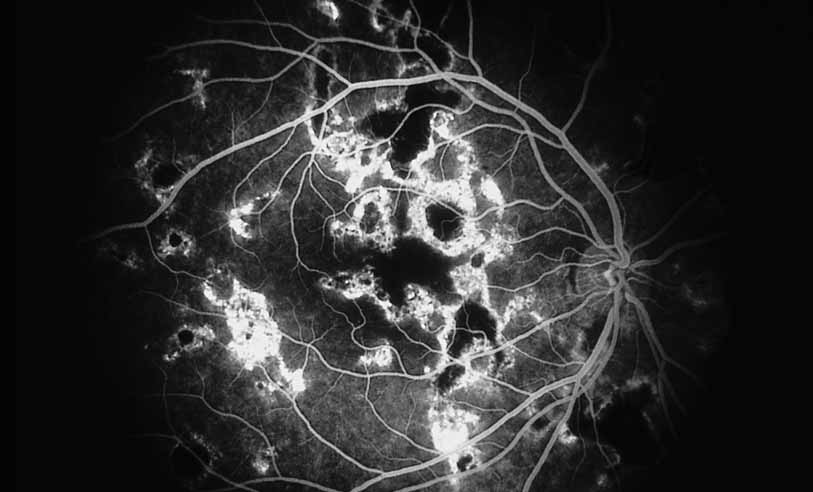

A third instance in which fluorescein angiography concentrating on the optic nerve may be helpful is in eyes with vascular engorgement of the optic nerve, especially with media opacities. Fluorescein angiography may help the clinician distinguish abnormally leaking capillaries from neovascularization. In acute multifocal hemorrhagic retinal vasculitis, optic nerve involvement is common in the early stages of the disease, 47 with optic nerve disc neovascularization seen later (see Figs. 10, 11, 12, and 13). Another fluorescein angiographic clue to the distinction between optic disc vessel engorgement and true neovascularization is the presence of associated large zones of retinal capillary nonperfusion such as those seen in sarcoidosis (see Figs. 14 and 15),34–40 acute multifocal hemorrhagic retinal vasculitis (see Figs. 10 and 11),47 or Eale disease (see Figs. 16 and 17).48–52

Fig. 11 Acute multifocal hemorrhagic retinal vasculitis. Fluorescein angiogram confirms the presence of associated retinal capillary non-perfusion without neovascularization at the onset of the disease.

Fig. 12 Acute multifocal hemorrhagic retinal vasculitis. The patient later developed disk neovascularization with vitreous hemorrhage. Note the areas of neovascular leakage from the optic nerve.

Fig. 13 Acute multifocal hemorrhagic retinal vasculitis. The patient underwent scatter laser photocoagulation to the zones of retinal capillary nonperfusion, which resulted in regression of the neovascularization.